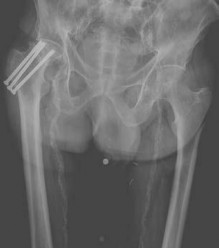

Figures 15a and 15b are the 6-week postsurgical anteroposterior hip radiograph and current radiograph of a 54-year-old avid hiker who returns for routine follow-up 3 years after an uncomplicated uncemented modular metal-on-metal hip replacement. He reports mild activity-related aching diffusely around the right hip region, but does not feel restricted with his activities. Examination reveals no local tenderness, a well-healed incision, and mild discomfort at the extremes of rotation. An erythrocyte sedimentation rate (ESR) and C-reactive protein (CRP) are obtained, showing 9 mm/h (reference range, 0-20 mm/h) and 2.0 mg/L (reference range, 0.08-3.1 mg/L), respectively. What is the etiology of the radiographic finding?

---

Explanation

The radiograph shows a large area of osteolysis involving the proximal femur. The implants appear solidly fixed on radiographs and, in the absence of symptoms, it is unlikely the implants are loose or infected. Although infection or metastatic disease is a possibility, the normal ESR and CRP values make the diagnosis of deep infection unlikely. The most likely cause for the radiographic findings is wear from metal particles resulting in an adverse local tissue response and osteolysis.